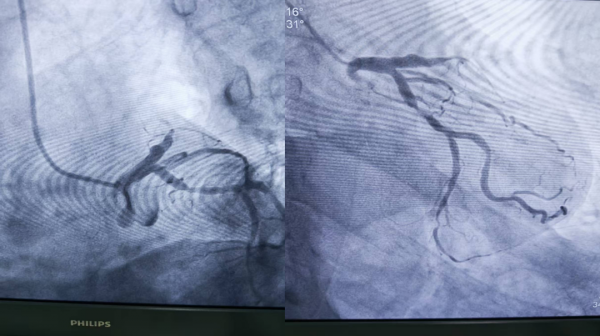

1、39歲男性,前降支閉塞,行血栓抽吸+冠脈內溶栓。

2、71歲男性,右冠閉塞,行藥物球囊擴張成形術。

3、69歲男性,雙支病變,行介入治療。